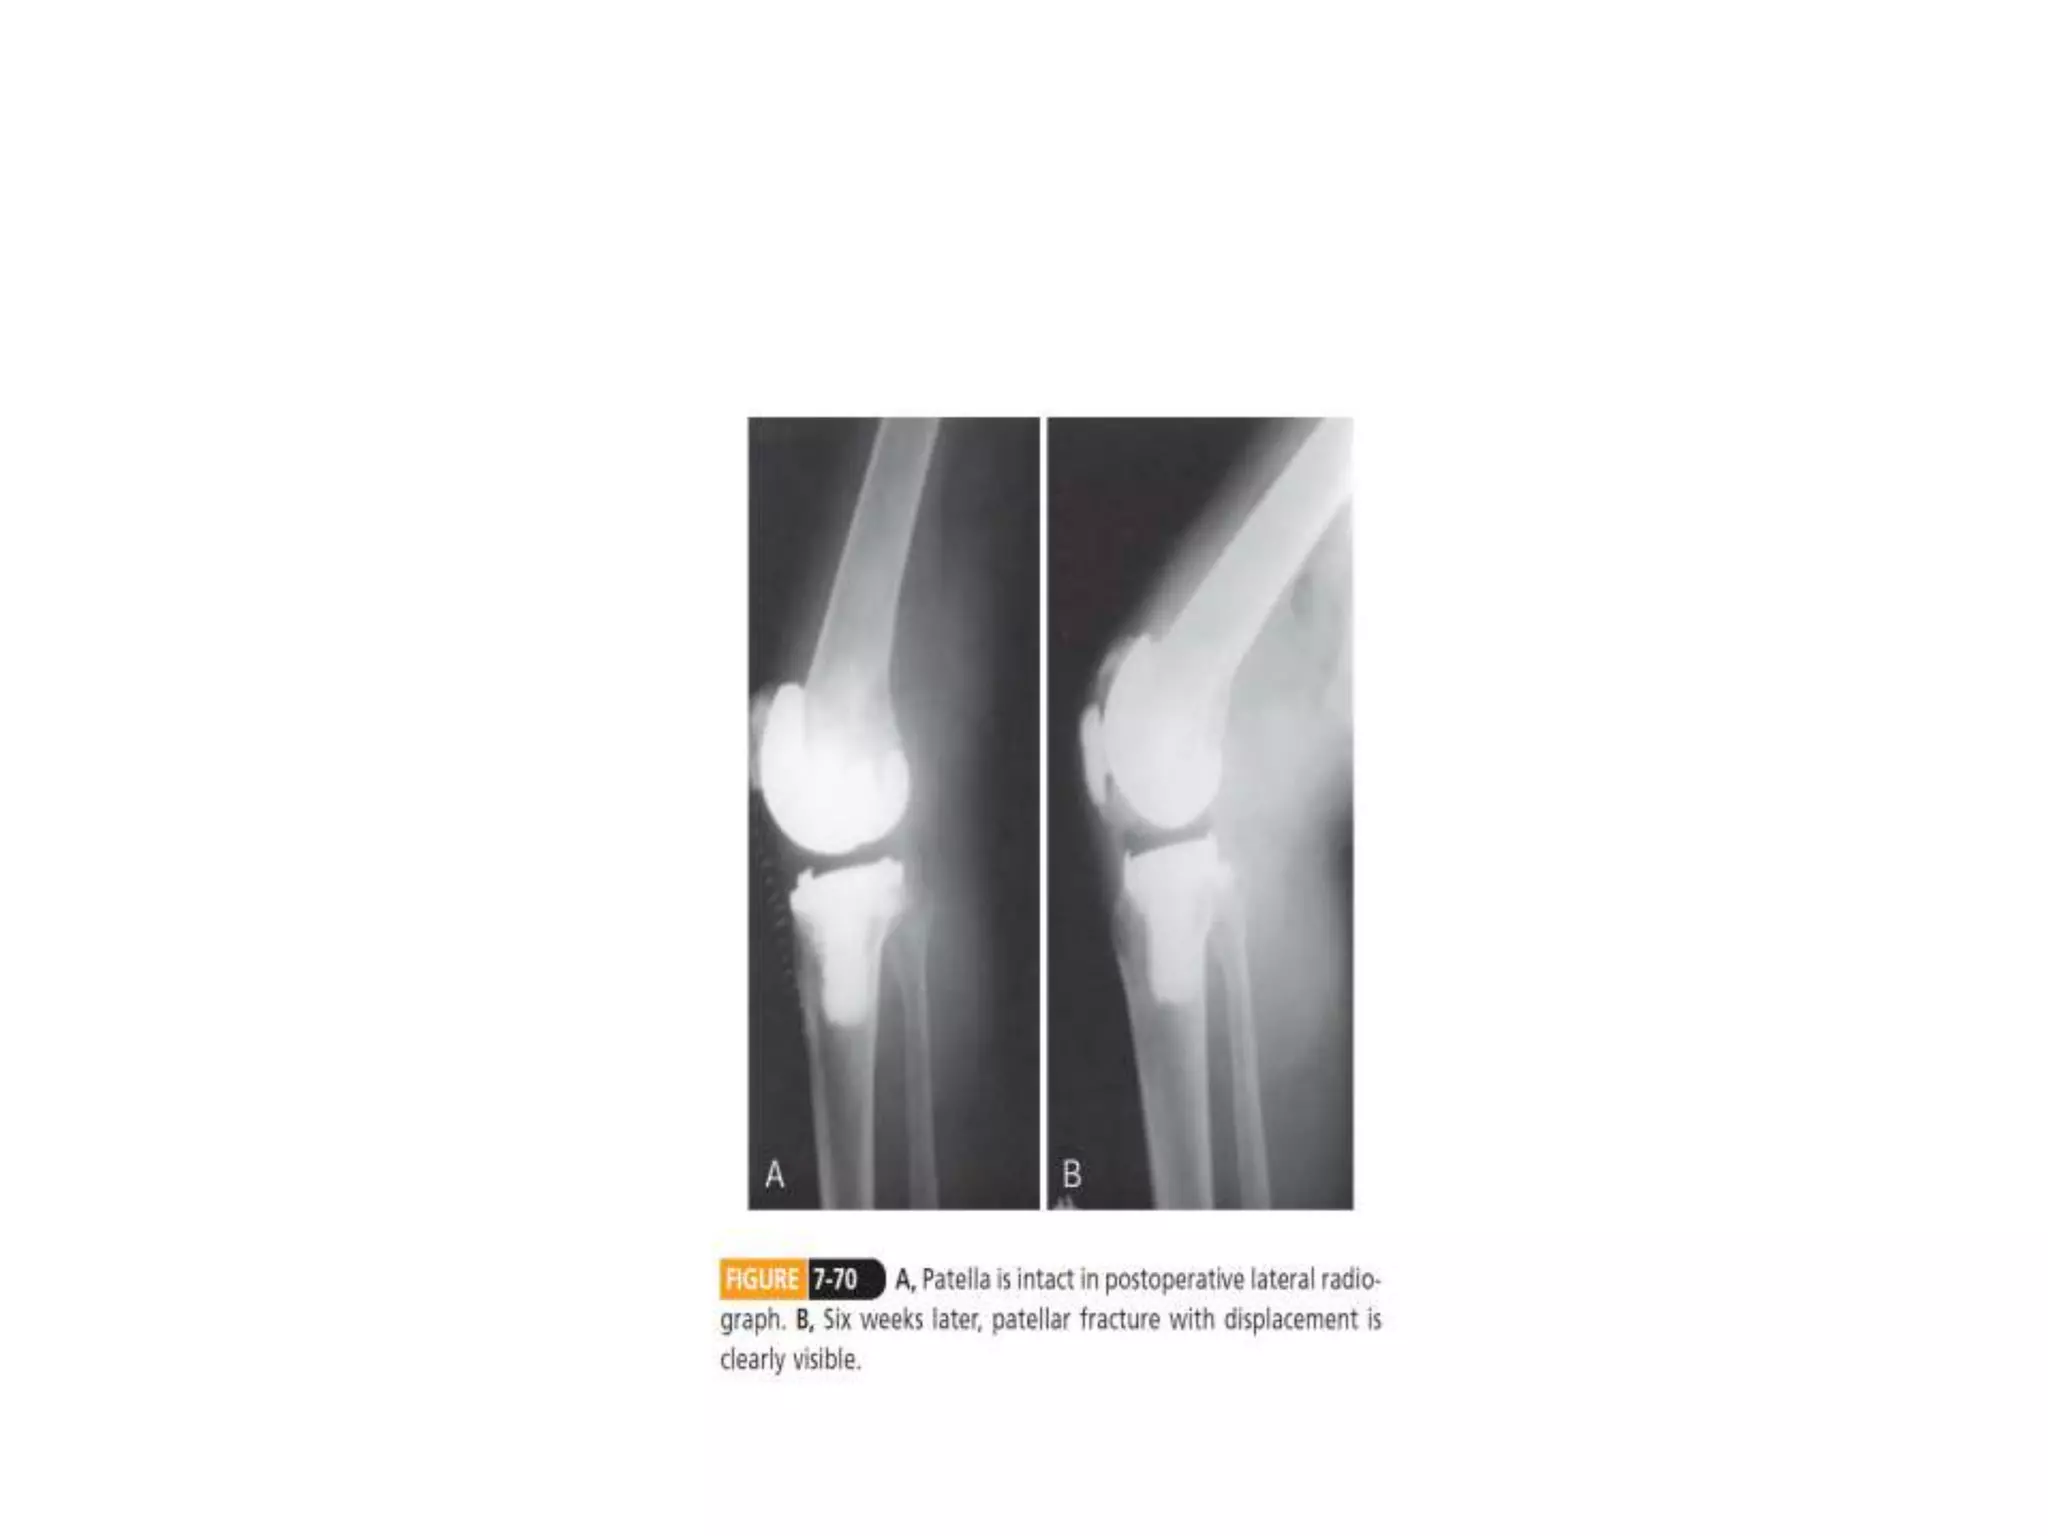

• Patellofemoral instability –Extensor mechanism imbalance – Mispositioned patellar, femoral or tibial components – Patellar subluxation • Patellar fracture – Uncommon, 1% – Excessive patellar resection – Vascular compromise secondary to lateral release – Patellar maltracking secondary to component malposition – Excessive joint line elevation – Knee flexion more than 115degrees – Trauma, thermal necrosis – Revision TKR

• 46.

• Patellar componentfailure – Fatigue fracture pf the metal baseplate from the fixation lugs – Delamination of the polyethyelene from the base plate • Patellar component loosening – 0.6-2.4% – Predisposing factors: deficient bone stock, component malposition and subluxation, patellar fractures, osteonecrosis of the patella, loosening of other components